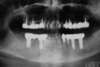

Extraction d'un bloc inscisif maxillaire naturel, pose de 10 implants complémentaires à ceux existants postérieurs (technique de "Summers") et réalisation d'un bridge complet maxillaire céramique sur implant fixe.

Armature métallique d'un cas complet mandibulaire, dents naturelles et implants